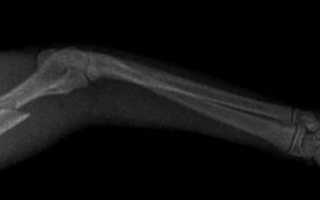

image

Диагностика в ветклинике

Если питомец получил травму, важно обратиться в ветеринарную клинику. Ветеринар осмотрит животное и проведет необходимые диагностические исследования, чтобы определить степень повреждения и назначить лечение.

К методам диагностики относятся общий и биохимический анализы крови, рентген в двух проекциях и ЭХО сердца. В некоторых случаях может потребоваться УЗИ брюшной полости.